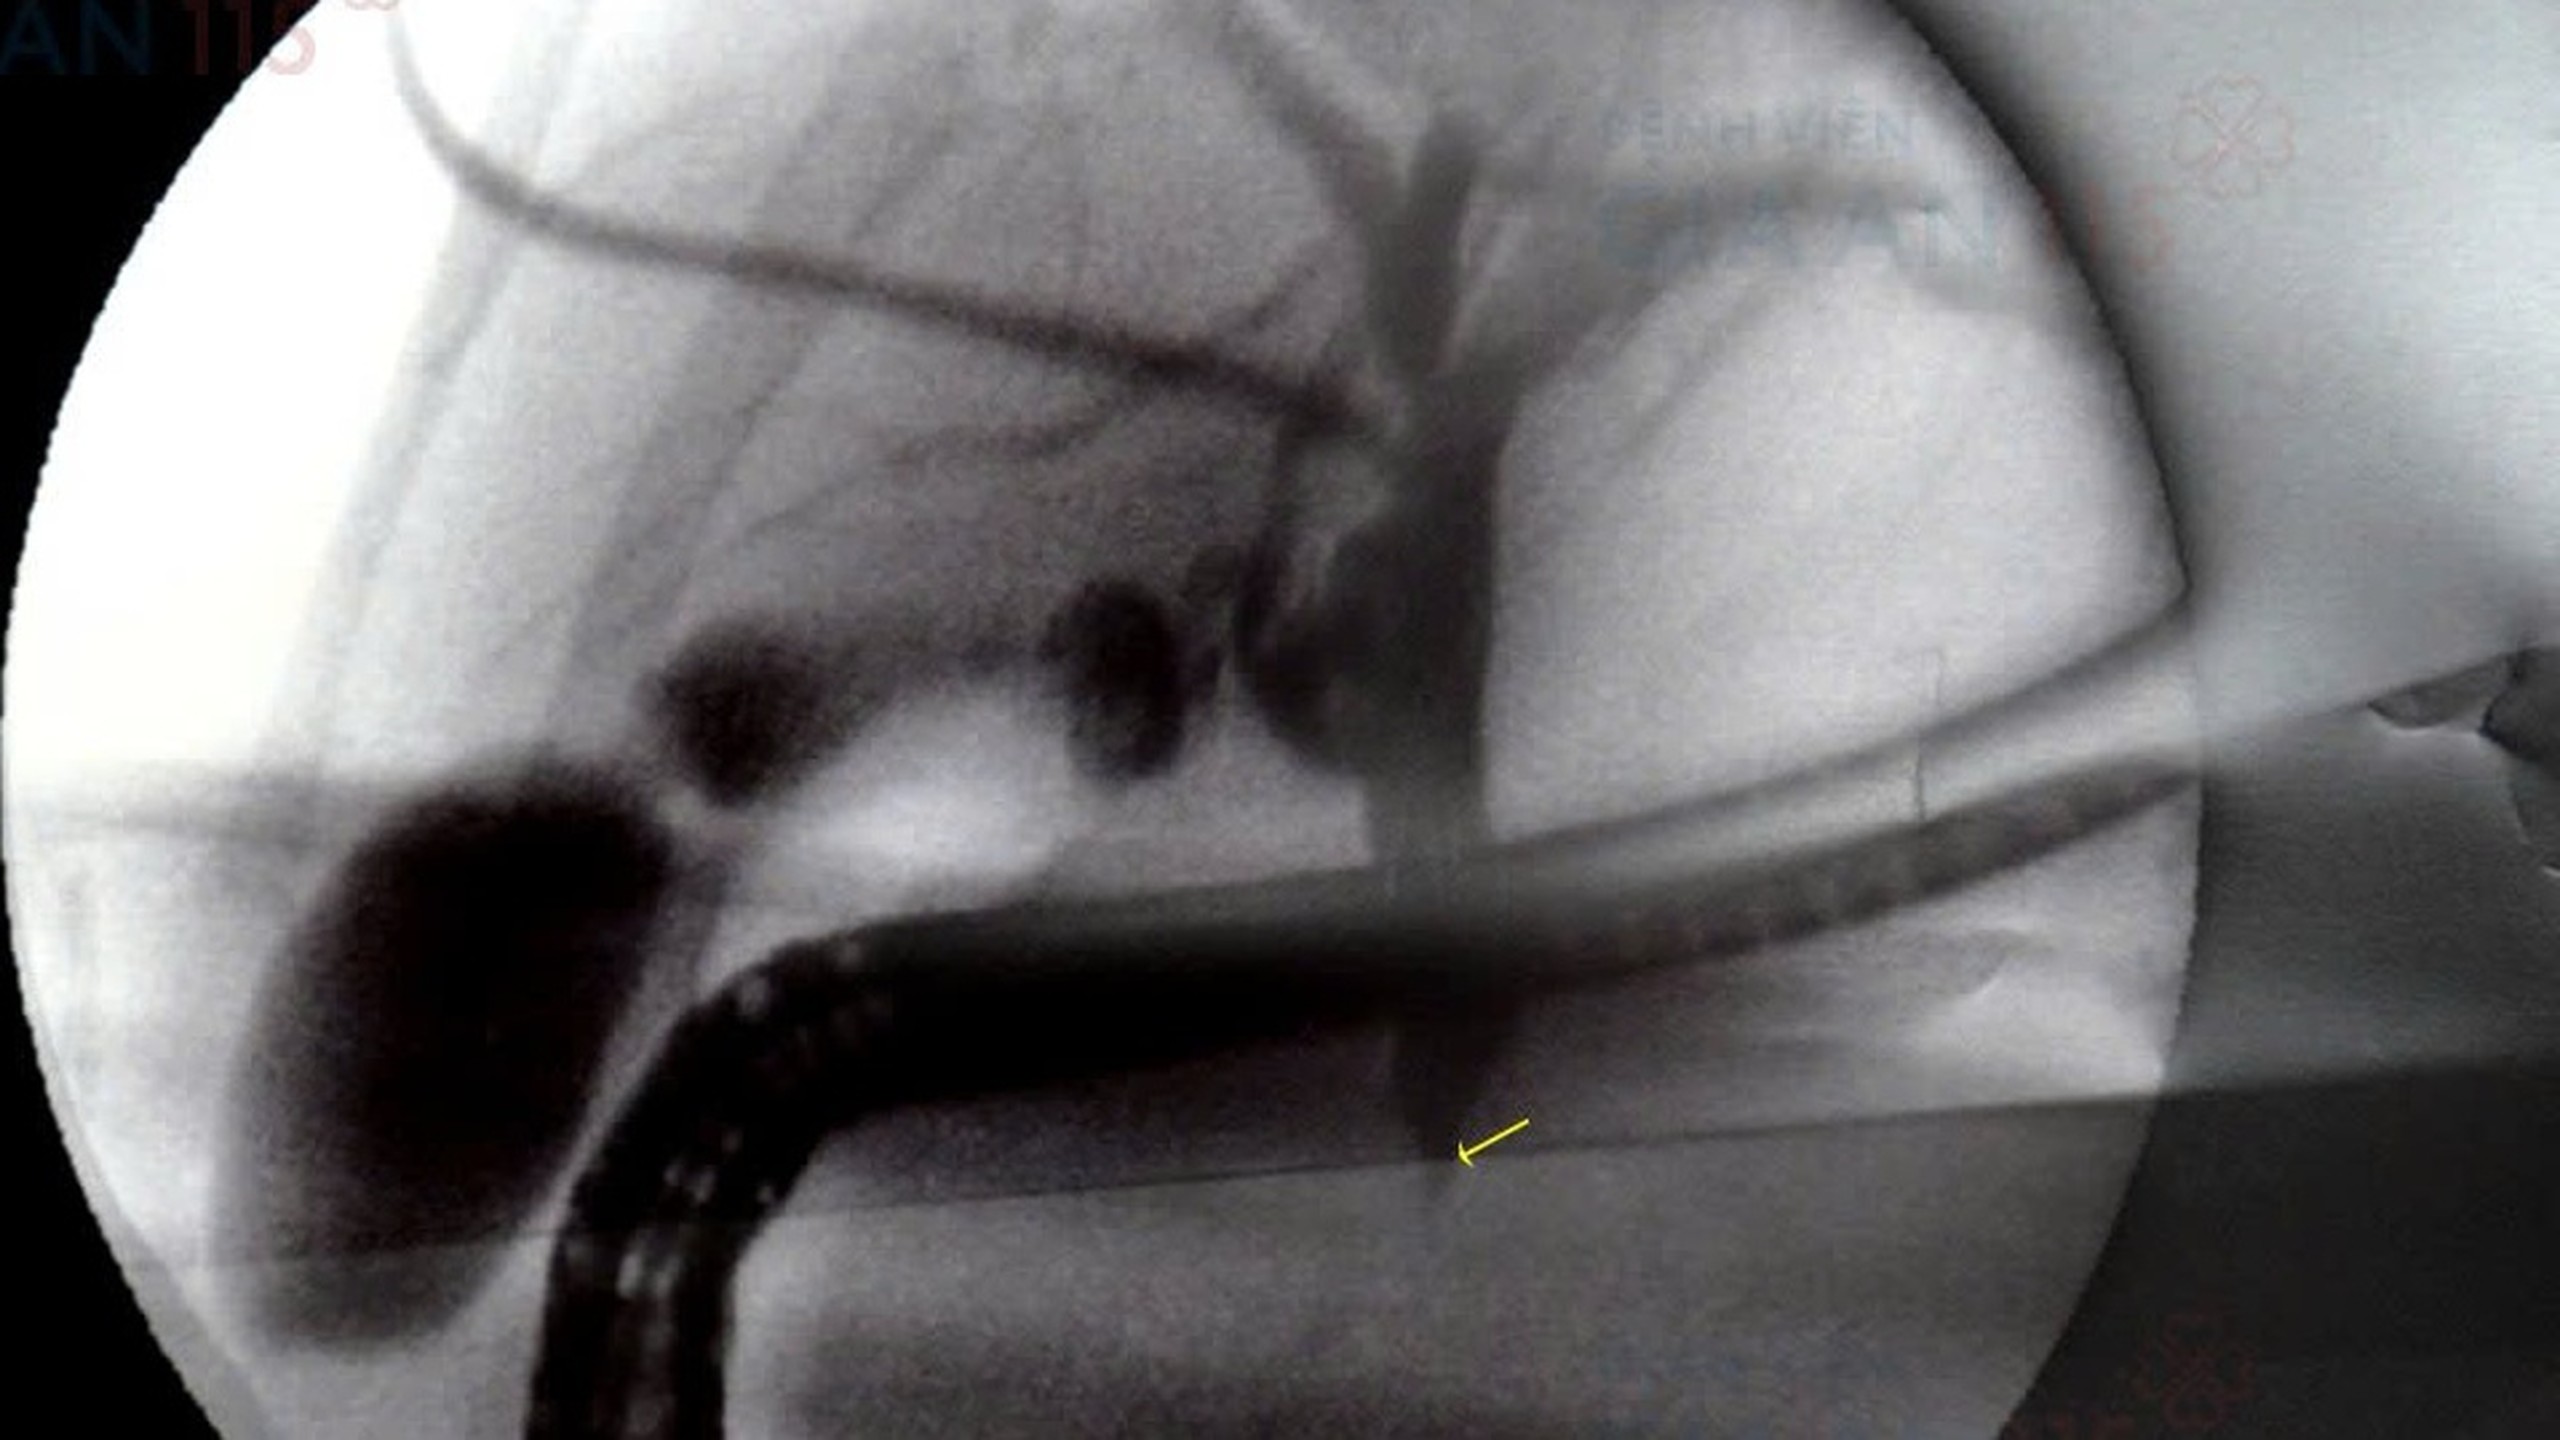

Tắc mật là tình trạng một hay nhiều ống dẫn mật bị tắc nghẽn, dẫn đến làm tăng nồng độ bilirubin và gây ra một số triệu chứng khác. Phụ nữ có nguy cơ cao mắc bệnh hơn, tuy nhiên cũng không loại trừ khả năng mắc bệnh ở nam giới, đặc biệt là những người có bệnh gan, béo phì… Nếu không tiến hành điều trị phù hợp, tắc mật có thể dẫn đến nhiều biến chứng khác ảnh hưởng xấu đến sức khỏe bệnh nhân.

Tắc mật là sự tắc nghẽn ở bất kỳ vị trí nào của ống dẫn mật khi mang mật từ gan đến túi mật hoặc từ túi mật đến ruột non, khiến mật tích tụ lại trong gan.

Nguyên nhân nội sinh: Bệnh sỏi mật (là nguyên nhân phổ biến nhất gây tắc mật), u, teo đường mật, nhiễm ký sinh trùng, viêm đường mật xơ cứng nguyên phát (PSC), bệnh đường mật liên quan đến AIDS, bệnh lao mật, hẹp đường mật, nang đường mật gây tắc mật chức năng.

Nguyên nhân ngoại sinh: Sự chèn ép bên ngoài ống dẫn mật do khối u, viêm tụy (cấp tính và mạn tính), nang giả tụy, tổn thương sau phẫu thuật cắt túi mật, hậu quả của tăng áp lực tĩnh mạch cửa, sỏi đường mật dẫn đến căng túi mật sau đó.